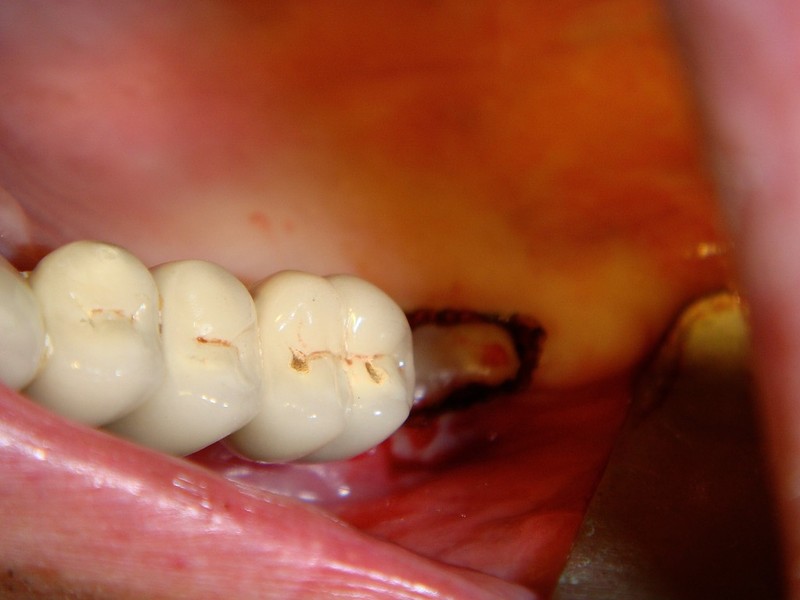

rigenerazione grave difetto parodontale a carico del 46